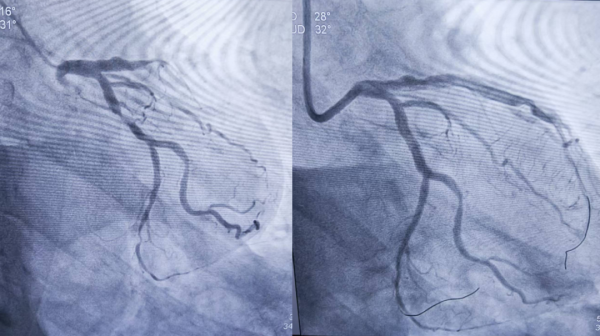

1、39岁男性,前降支闭塞,行血栓抽吸+冠脉内溶栓。

2、71岁男性,右冠闭塞,行药物球囊扩张成形术。

3、69岁男性,双支病变,行介入治疗。